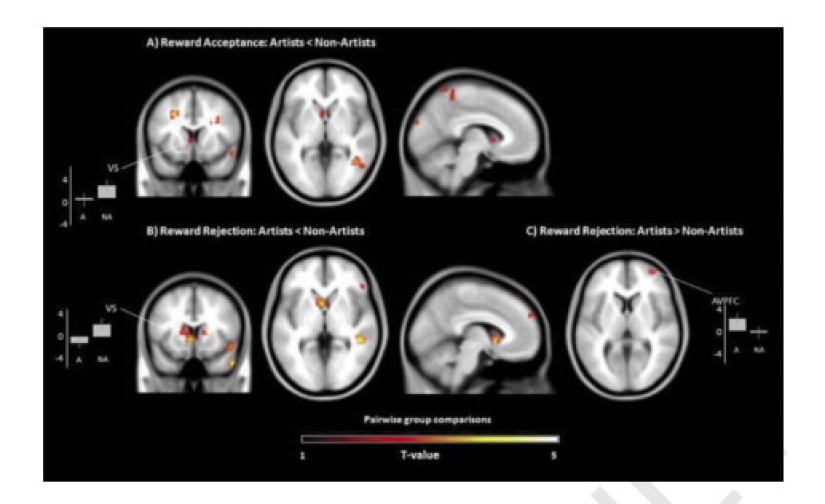

And here is the result. Creative people, seeing green, bring money, showed very low activity in the area of stripe body — this area of the brain responsible for rewards. If free artists seen free color, the machine recorded high activity in the prefrontal cortex — this division is responsible for the production of dopamine which, in turn, causes a feeling of satisfaction.